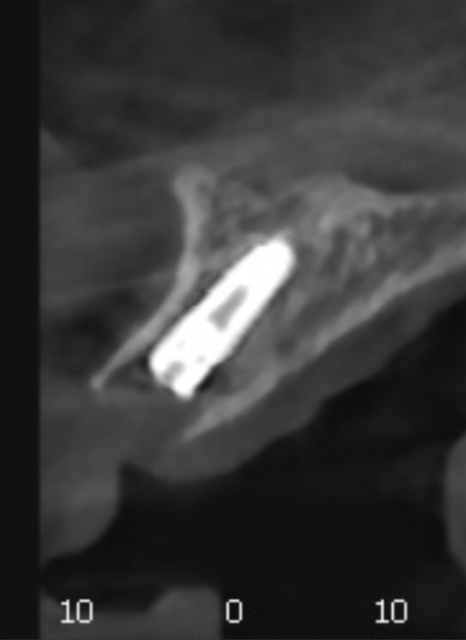

수술 후 4개월이 지나 임플란트와 뼈가

단단히 결합된 것을 확인했습니다.

이제 마지막으로 임플란트

보철물을 만드는 단계를 거치는데요.

3D 구강 스캐너로 얻은 정밀한 데이터는

컴퓨터상에서 입체적인 모델로 구현됩니다.

사진 속에 보이는

파란색 기둥들은 스캔 바디라고 부르는데요,

잇몸 속에 심어진 임플란트가

어느 깊이와 각도로 자리 잡고 있는지

컴퓨터가 정확하게 인식할 수 있도록

도와주는 이정표 역할을 하죠.

이렇게 확보된 디지털 데이터를 바탕으로

환자분의 얼굴형과 주변 치아에

가장 잘 어울리는 모양을 정교하게 설계합니다.

사진 속 노란색 치아들이

바로 환자분의 새로운 앞니가 될 디자인이에요.

컴퓨터상에서 대칭과 비율을 0.1mm 단위까지

세밀하게 조정하기 때문에,

인위적인 느낌 없이 본래 내 치아처럼

자연스러운 결과물을 기대할 수 있습니다.